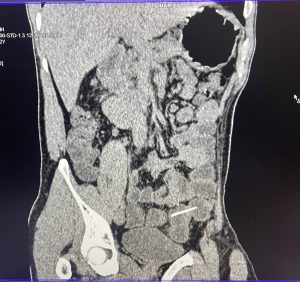

Vừa qua, Khoa Ngoại Bệnh viện Đa khoa Bố Hạ tiếp nhận bệnh nhân đến khám trong tình trạng đau bụng, đau bụng tăng dần. Bệnh nhân được khám và thực hiện các kỹ thuật chẩn đoán chuyên sâu trong đó có chụp CT Scanner phát hiện có dị vật trong đại tràng và được chỉ định nội soi tiêu hóa gây mê lấy dị vật.

Trong quá trình nội soi đại tràng gây mê, kiểm tra thấy đoạn cuối đại tràng sigma có 2 dị vật dài. Các bác sĩ đã tiến hành gắp dị vật nghi ngờ là xương gà ra ngoài. Sau khi nội soi gắp dị vật, bệnh nhân không còn đau, có thể ăn uống bình thường.